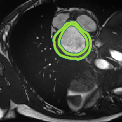

Despite their outstanding accuracy, semi-supervised segmentation methods based on deep neural networks can still yield predictions that are considered anatomically impossible by clinicians, for instance, containing holes or disconnected regions. To solve this problem, we present a Context-aware Virtual Adversarial Training (CaVAT) method for generating anatomically plausible segmentation. Unlike approaches focusing solely on accuracy, our method also considers complex topological constraints like connectivity which cannot be easily modeled in a differentiable loss function. We use adversarial training to generate examples violating the constraints, so the network can learn to avoid making such incorrect predictions on new examples, and employ the Reinforce algorithm to handle non-differentiable segmentation constraints. The proposed method offers a generic and efficient way to add any constraint on top of any segmentation network. Experiments on two clinically-relevant datasets show our method to produce segmentations that are both accurate and anatomically-plausible in terms of region connectivity.